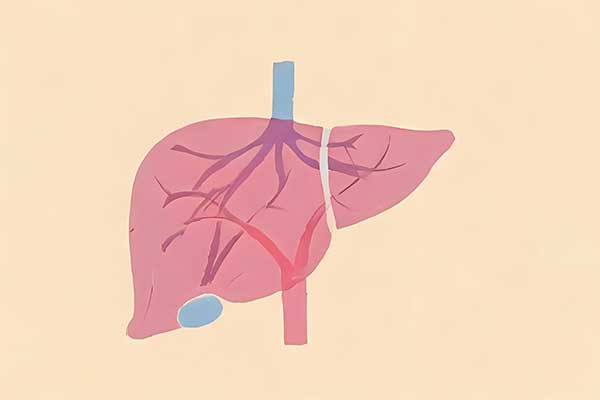

дёӯеҢ»еёёиҜҙзҡ„вҖңеҸ‘зү©вҖқеҲ°еә•жҳҜд»Җд№Ҳ

пјҹ

йғҪиҜҙз—…д»ҺеҸЈе…Ҙ

пјҢиҖҢйЈҹе“ҒдёӯиҝҳжңүеҸ‘зү©зҡ„иҜҙжі•гҖӮ